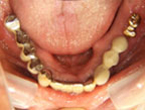

Case.01 骨造成インプラント治療症例

初診時

上下顎に数本の歯が残っていますが咬合支持がほとんどないために満足に食事もできない状態でした。また、下顎前歯部から臼歯部にかけて骨吸収が進行しており、上顎臼歯部にインプラント治療を行うためには骨造成が必要な状態です。

レントゲン